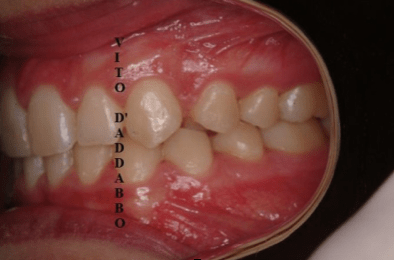

Non di rado accade che manchi in arcata il canino permanente superiore. Questo può essere dovuto a mancanza di spazio ma anche a problemi di eruzione del dente che si colloca lontano dalla propria sede. Nel caso di questa paziente, che presentava anche un grave morso coperto, il canino era dislocato palatalmente e molto distante dalla propria sede. Previo un piccolo intervento chirurgico è stato agganciato e portato in arcata.

prima